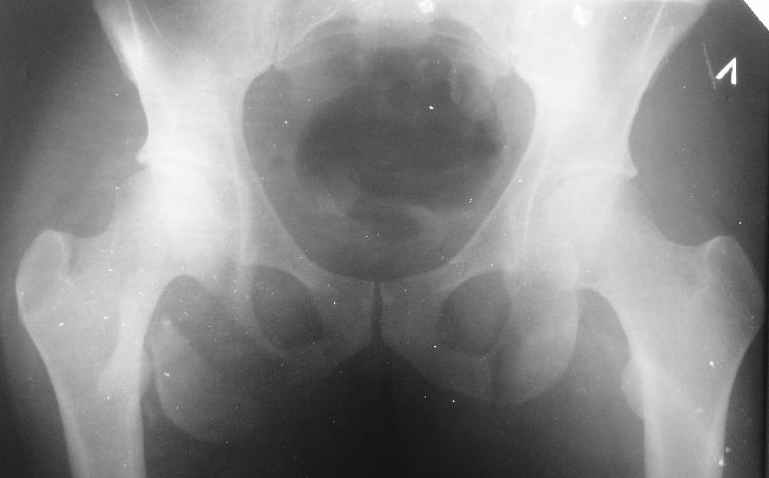

Уважаемые коллеги, хотелось бы услышать ваше мнение по тактике лечения следующего пациента: мужчина, 27 лет, получил травму на производстве 25 июня - перелом правого седалищного бугра (кт и рентгенограмма прилагаются).

Больной жалуется на боли - сидя и при ходьбе. В

настоящее время ходит, хромая, без дополнительной опоры. Оторвавшийся седалищный бугор состоит из 2-х фрагментов, один из которых раздражает седалищный нерв. Если кто-то имеет опыт оперативного лечения подобных повреждений, подскажите из какого доступа лучше это сделать. Заранее спасибо.